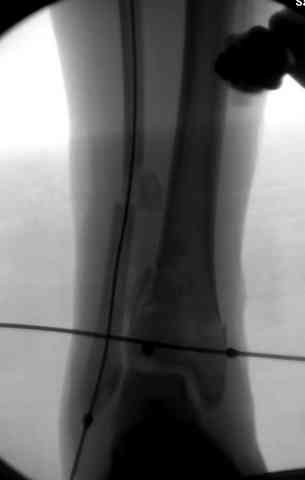

Снова приветствую вас, коллеги. К моменту вступления в обсуждение аксакалов, операция была, увы, выполнена(31.10.07.) Начали с доступа к наружной лодыжке, произвели ее фиксацию спицами, развернули кусок заднего края, наложили дистрактор, затем произвели дистракцию, фиксацию спицами дистального эпиметафиза б/бк,Рентгено-контроль. синтез наружной лодыжки 1/3пластиной. из двух коротких разрезов сформирован канал под медиальную тибиальную пластину LCP. Края ран ушиты без натяжения. Прочувствовать жесткость фиксации винтами с угловой стабильностью не удалось, поэтому дистрактор оставлен на энное время.

На представленных R-снимках не окончательный вид после остеосинтеза. Дистальная опора давила на стопу, пришлось ее сместить проксимально, в рез-те чего, она закрыла щель сустава, последние снимки не информативны.

Причина нарастающего отёка скорее всего нестабильная фиксация,либо начинающая инфекция.

У меня вопрос. Почему проксимальный фрагмент с медиально стороны фиксированк плате всего одним болтом.

Дистальные винты как-то чуть не все идут не в дистальные отломки, а в зону перелома. И действительно, присоединяюсь к вопросу Якова - в диафизе так и оставили 1 винт?